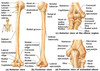

Scapula label

Where is scapula connected to clavicle?

What does it form with clavicle?

Acromion

Shoulder gridle

Two joints of clavicle

Sternoclavicular joint

Acromioclavicular joint

Label ligaments

Where does the shoulder separation occur?

WHere does the shoulder dislocation occur?

Where does the clavicle break most often?

AC joint

glenohumeral joint

Middle/lateral thirds